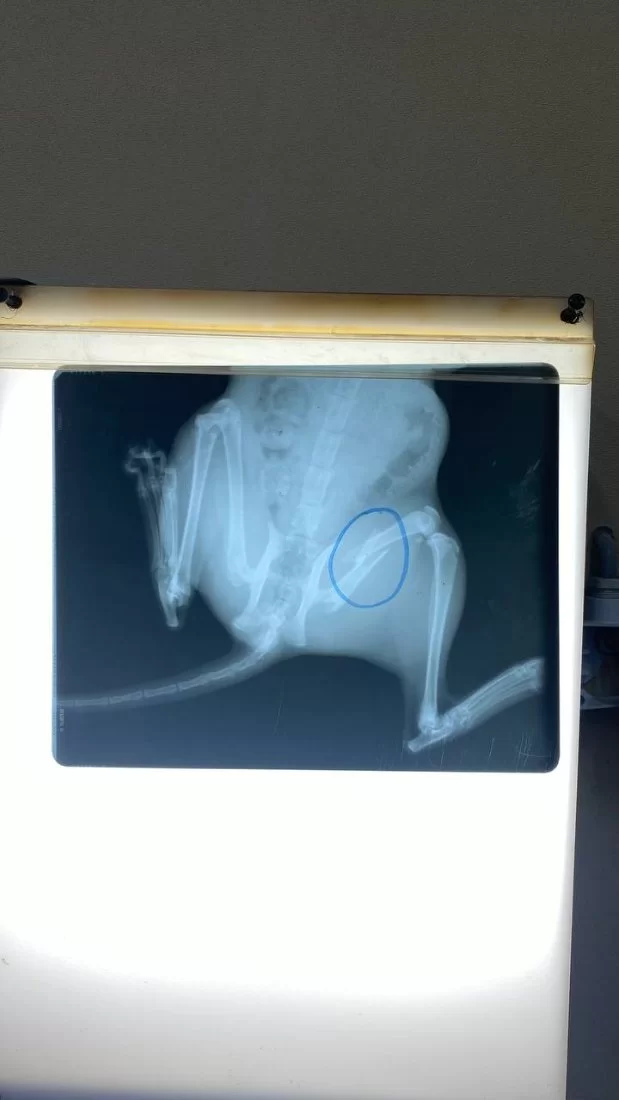

حالة الكلب روكي ( المذبوح)

تم استقبال الكلب روكي بكلية الطب البيطري جامعة طرابلس قسم الجراحة والتخدير والأشعة. كان روكي في حالة يرثى لها من جفاف حاد وضعف عام ووهن. كان يعاني من جرح عميق في الرقبة (ذبح) حيث كان اي طعام او ماء يدخل عن طريق الفم يخرج من هذا الجرح ولايستفيد منه جسم روكي. تم على ال